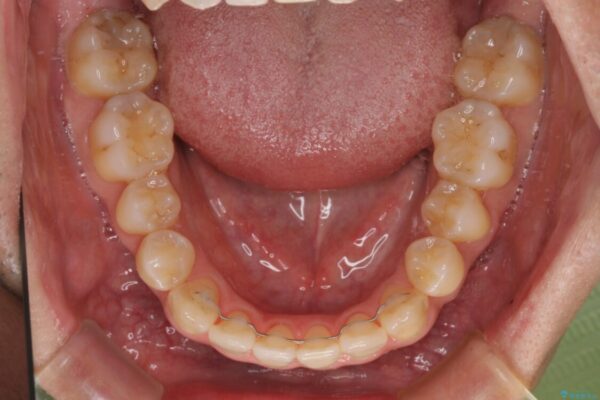

治療前

• 左右の八重歯が気になる ワイヤー装置での咬み合わせ改善 治療前画像